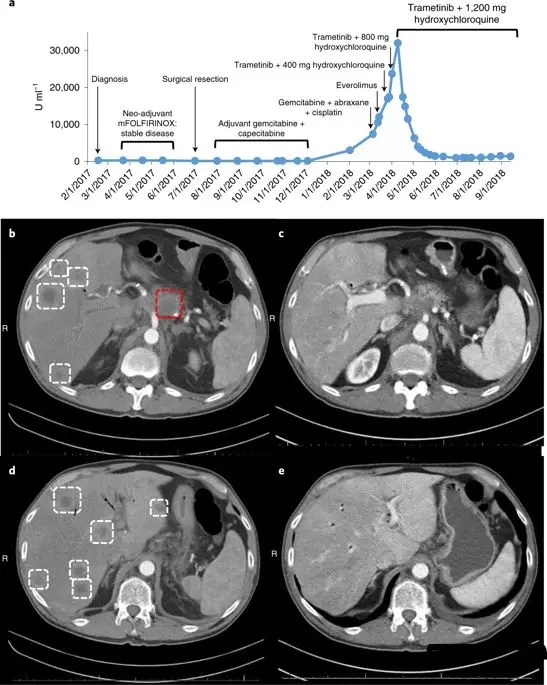

除了安进公司的AMG 510外,一种称为羟氯喹的自噬抑制剂和一种阻断MAPK途径中蛋白质的药物trametinib(曲美替尼 Mekinist)一起治疗可以减缓在移植了KRAS- 突变的人胰腺肿瘤的小鼠中肿瘤生长并延长存活时间。

用曲美替尼和羟氯喹治疗移植了胰腺肿瘤的小鼠,结果显示肿瘤一致消退。

这种联合疗法的效果在一位晚期胰腺癌患者身上同样得到了证实,这位患者在手术后,接受了几次化疗,但不幸的是癌症复发并转移了,目前已经没有很好的治疗方案,

这名患者接受了 trametinib和hydroxychloroquine治疗,令患者和医生震惊的是,奇迹出现了,2个月内,患者的胰腺癌标志物CA 19-9的血液水平下降了95%。4个月后,他体内的癌症数量减少了50%。对于胰腺癌来说,这是一个非常了不起的反应!

用曲美替尼加羟氯喹(T / HCQ)治疗胰腺癌患者导致肿瘤标志物癌抗原19-9(CA19-9)和总体肿瘤负荷减少。